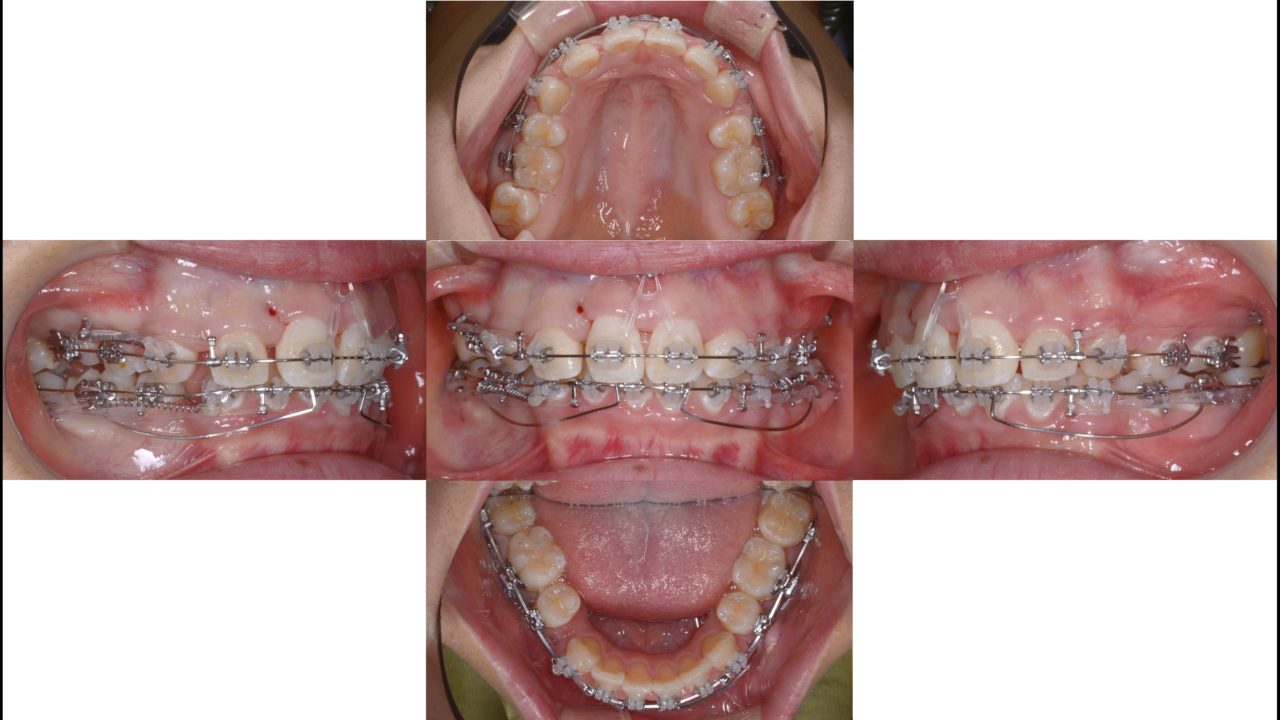

矯正開始10か月 2019.4.16

| 備考 | 小学生のときに他院で第1期矯正をされていました。歯の凸凹は治り歯列はきれいになりましたが、全体的に前に出た仕上がりに不満を持っていました。成長の予測が難しい第1期矯正において、起こりうることです。口元をきれいに引っ込めるために抜歯を伴う矯正治療をすることになりました。第1小臼歯を4本抜歯し、矯正用インプラントにてできるだけ前歯を後方に移動しました。口元が引っ込み、とてもきれいになりました。矯正治療のやり直しはできればしたくないし、さらに結果が求められるので大変ですが、良い結果が出てよかったです。 |